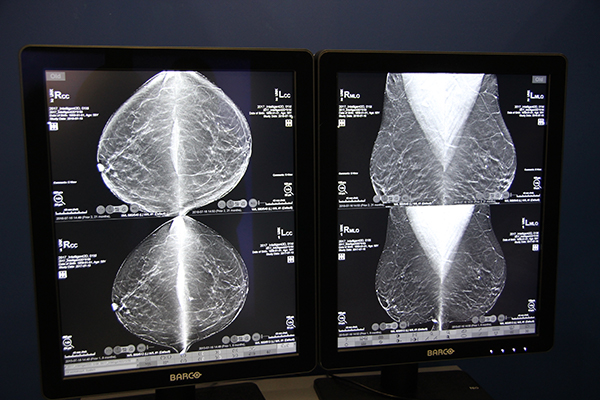

高画質化については,新開発のトモシンセシス画像再構成アルゴリズム“ClarityHD”により,トモシンセシスの画素サイズが従来の100μmから70μmへと高精細化したことで,従来よりも鮮鋭度と粒状性の高い画像を取得可能になった。また,高画質化したトモシンセシス画像から作成される合成2Dの“Intelligent 2D”は,従来の合成2Dで弱点とされていた微小石灰化やスキンラインの描出,関心領域のアーチファクトなどが改善され,通常の2Dに近い画像を提供する。

鮮鋭度と粒状性が向上したトモシンセシス画像から合成された“Intelligent 2D”